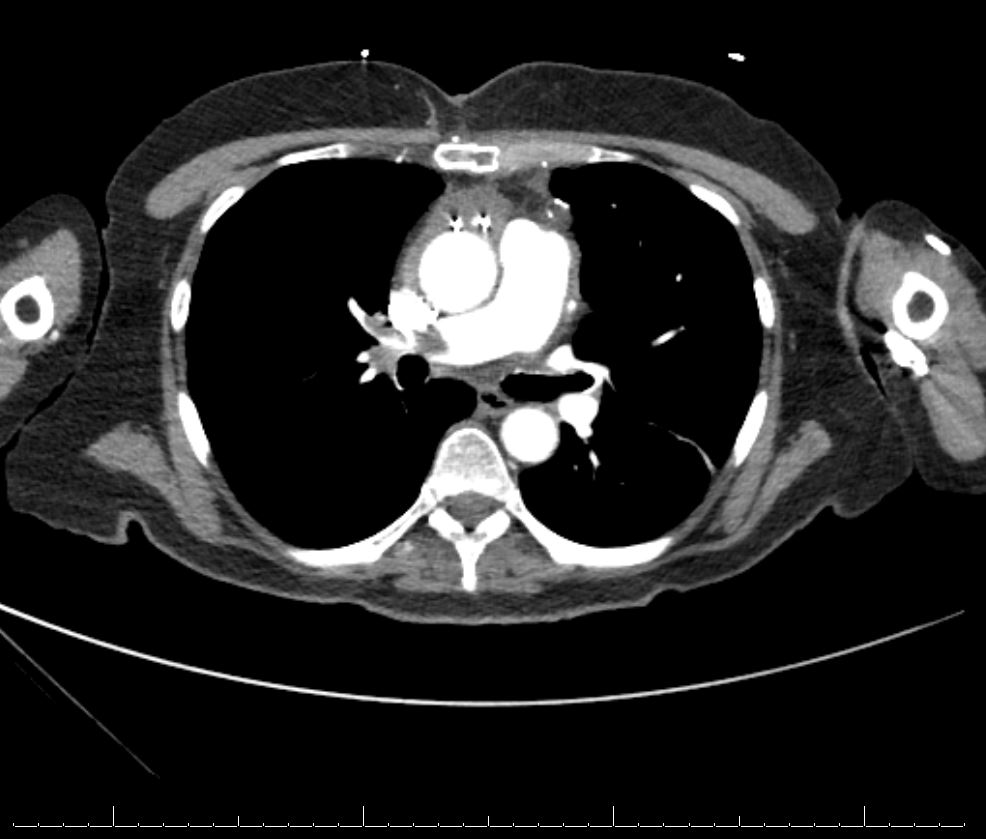

Case Presentation: A 66 year old female with a past medical history of hypertension (HTN), hyperlipidemia (HLD) and coronary artery disease (CAD) presented to the hospital for an elective three-vessel coronary artery bypass graft involving the left internal mammary artery to left anterior descending artery, saphenous vein graft (SVG) to the obtuse marginal artery, and SVG to the posterior descending artery. During the CABG, she received 2700 units of heparin. On post operative day (POD) seven she was discharged home. On POD nine, the patient presented back to the emergency department with pain, swelling, and erythema to the left lower extremity. An ultrasound of her lower extremities revealed an occlusive clot burden from the left popliteal to the common femoral vein. A heparin drip was initiated. A Chest CT was obtained with angiography and revealed an acute large burden, occlusive and non-occlusive pulmonary embolisms (PE), and associated right heart strain. The pulmonary embolism response team (PERT) was activated, and the patient underwent urgent mechanical thrombectomy by interventional radiology. Interestingly, initial lab work revealed a decrease in platelets from 209 on her previous discharge to 82 at the time of re-presentation. The combination of thrombosis and thrombocytopenia raised the concern for heparin induced thrombocytopenia (HIT). A HIT Expert Probability (HEP) score was calculated and found to be elevated. The initial heparin drip was stopped and she was transitioned to Fondaparinux. A HIT antibody screen and serotonin-release assay (SRA) subsequently confirmed the diagnosis.